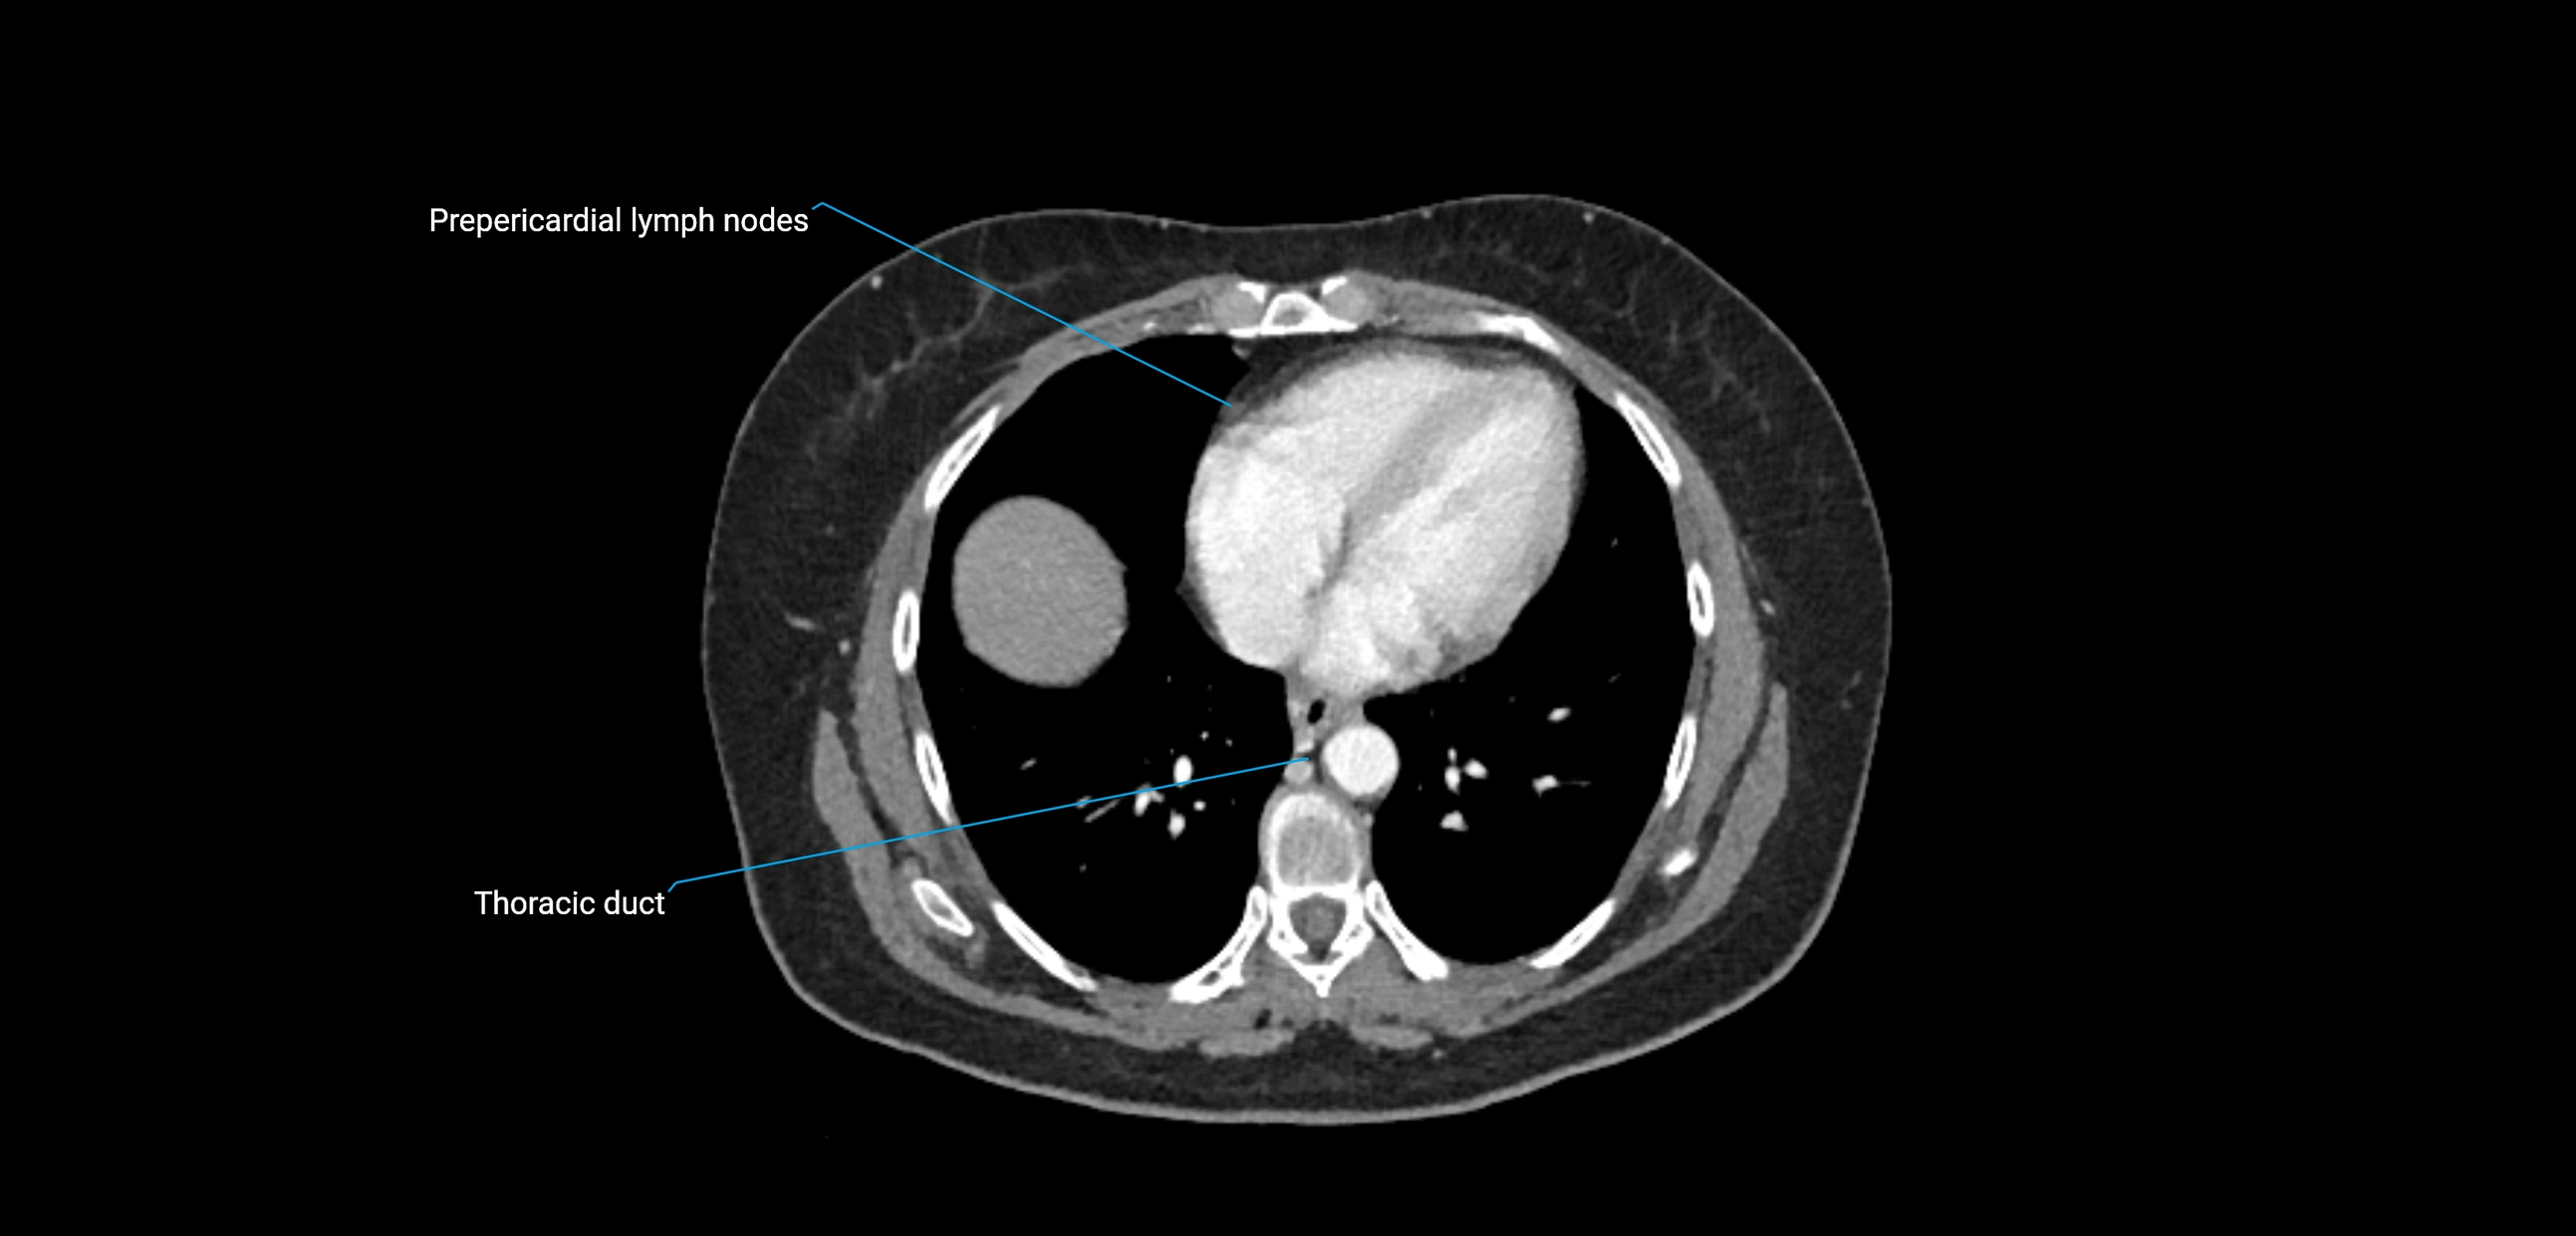

CT Appearance

CT Pre-Contrast:

• Nodes appear as soft-tissue density nodules adjacent to the aorta and IVC

• Calcification may be seen in chronic infections (e.g., tuberculosis)

CT Post-Contrast:

• Normal nodes enhance homogeneously

• Malignant nodes may show heterogeneous enhancement, central necrosis, or conglomerate formation

• Size >1 cm short axis is suspicious, though morphology and distribution are equally important